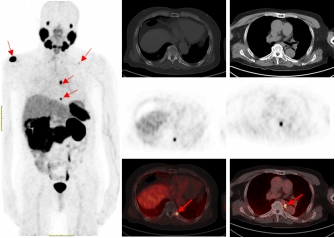

PSMA-PET/CT利用靶向核素分子影像优势,可识别最大直径为4毫米甚至更小的转移淋巴结,68Ga标记的PSMA-PET/CT诊断骨转移灶敏感性更高,能比传统检查手段早一步发现转移灶,为患者的精准治疗赢得时间。

一名75的岁男性患者自2019年确诊前列腺癌后,先后接受过两次内分泌治疗及前列腺癌根治术的综合治疗。在术后两年的复查中发现血PSA持续升高,CT检查和全身骨显像检查均未发现明显异常,医生建议随诊,患者来到p站

附属医院要求进一步检查。经核医学科68Ga-PSMA PET/CT检查后结果显示,双侧肩胛骨、左侧第9后肋、第2腰椎及纵隔淋巴结均已存在癌症转移。